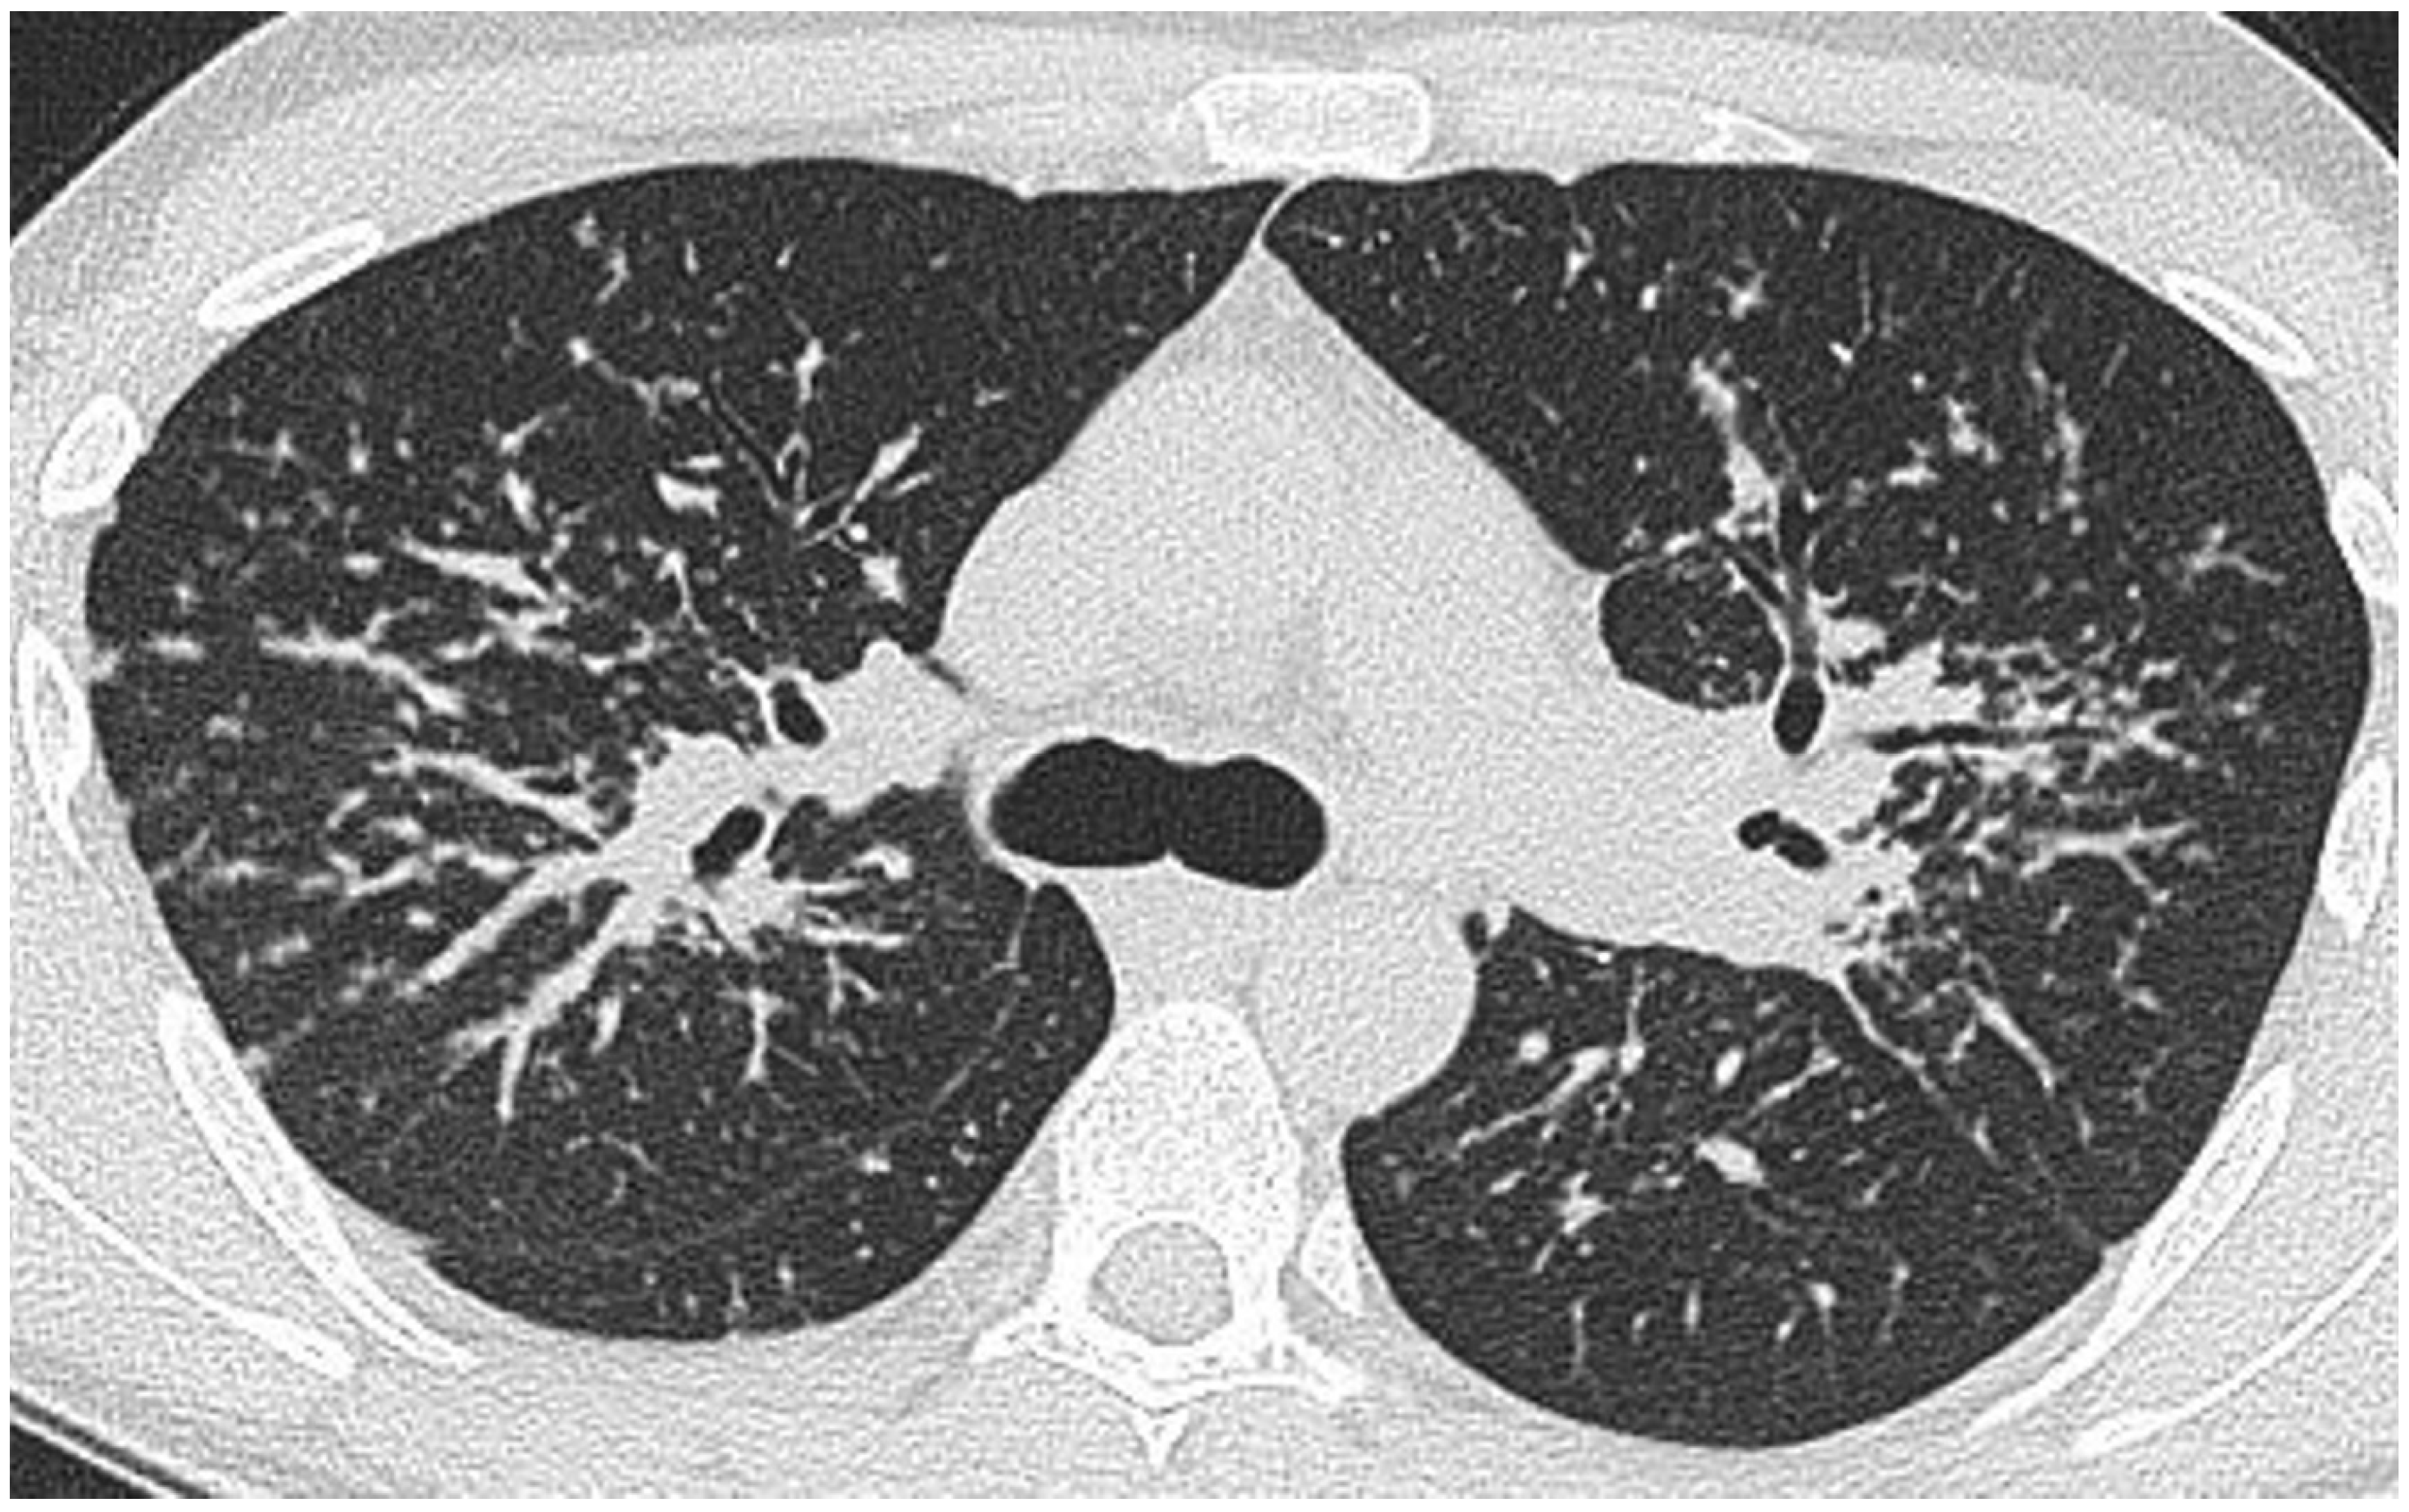

Figure 2.

CT at the level of the carina in the same patient as in Figure 1. There is a roughly symmetrical bronchocentric micronodular infiltrate. More centrally, there is dense parenchymal opacification caused by conglomeration of nodules around the bronchovascular structures.